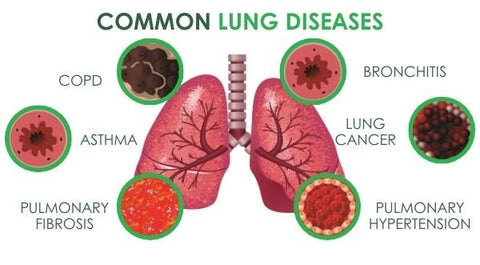

Understanding Lung health

It goes without saying that our lungs are two of the most important organs in our body. They are responsible for providing oxygen for every cell in the human body – meaning that functional lungs are necessary for healthy basic cell functions. The lungs also contract up to 20 times a minute, making them some of the hardest-working organs in the body.

But did you know that some of the most common habits we have can actually destroy our lungs? Here are the common habits that could be damaging your lungs: smoking, poor posture, not exercising, exposure to pollutants, and an unhealthy diet. e. Thankfully, Respira™ Lung Care Spray is developed to naturally support individuals with various lung conditions, providing relief, enhancing respiratory function, and promoting a healthier and happier life.